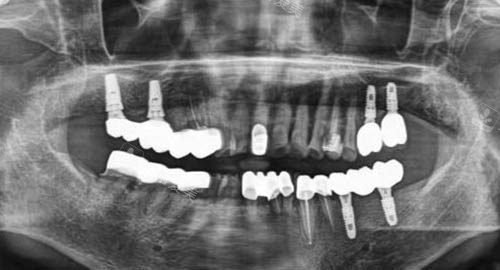

例如,在种植牙手术中,医师们能够更准一些地把握种植位置和角度,大大提高种植的成功几率,让患者重新拥有健康的牙齿。

而且,门诊部引进了新型的口腔诊疗设备,如口腔CT、智能化牙片机等,能够快速、更准地诊断患者的口腔问题,为治疗提供有力的支持。